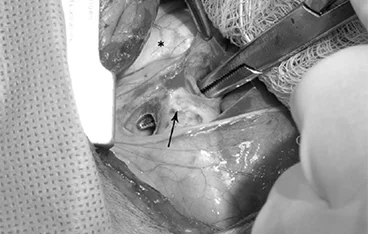

외이도 종괴, 외이염&중이염&내이염

TECA+LBO / VBO

• TECA+LBO 수술 전

TECA+LBO 수술 후